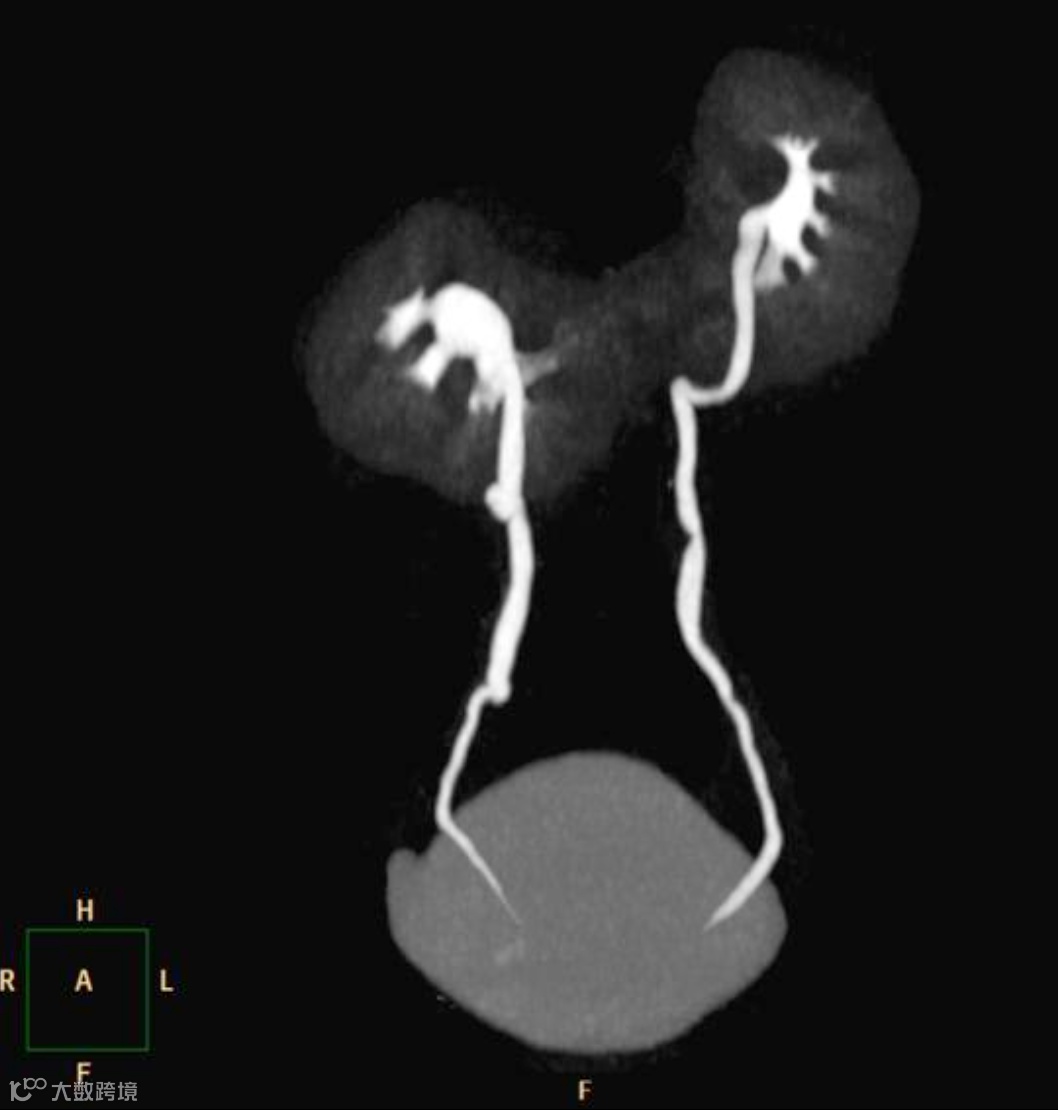

可直接、三维地清晰显示双肾下极在中线处的实质融合。

位置与融合:两肾下极(90%)或上极(10%)在中线处融合,形成峡部,峡部多位于腹主动脉前方。

旋转异常:肾门朝向前方或外侧,肾盂朝向前内侧,肾盏位于肾前方。

增强扫描:可清晰显示峡部血供来源,可能来自肾动脉、髂总动脉或肠系膜下动脉。

CTU能更清晰地显示旋转异常的肾盂肾盏和输尿管起始部。

女,25岁,马蹄肾。肾脏下极相连,呈马蹄形,肾皮质厚度正常,泌尿系统未见梗阻扩张。